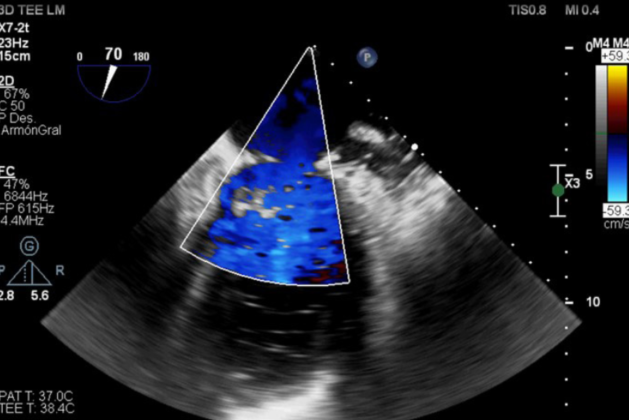

Con diagnóstico positivo de endocarditis infecciosa sobre válvula nativa mitral a S. aureus con insuficiencia mitral severa, se decide continuar con tratamiento quirúrgico. En la exploración intraoperatoria se observó una válvula mitral con degeneración mixomatosa del velo posterior y con rotura de varias cuerdas a nivel de festones P2 y P3. Se constató una pequeña vegetación a nivel de sitio de inserción de cuerda tendínea sobre músculo papilar posterior. Se llevó a cabo una plastia valvular mitral con colocación de tres neocuerdas (Chord-X) desde el músculo papilar posteromedial al sitio de rotura cordal. Como luego de realizar dicha reparación la válvula permanecía insuficiente frente a las maniobras hidráulicas, se decidió realizar resección cuadrangular del segmento valvular insuficiente y reconstrucción de este. Se implantó, además, un anillo mitral semirrígido de 34 mm. El ecocardiograma transesofágico intraoperatorio evidenció una válvula mitral estable, normofuncionante, sin fugas y con gradientes anterógrados adecuados (figura 3). El paciente evolucionó de manera favorable, sin complicaciones. Se otorgó alta precoz y continuó con tratamiento antibiótico ambulatorio. El ecocardiograma transtorácico de control evidenció una plastia mitral exitosa, con reducción de las dimensiones diastólicas del ventrículo izquierdo.

cocardiograma transesofágico intraoperatorio Doppler color. Se observa una plastia mitral efectiva, sin reflujo evidente y en ausencia de estenosis residual.

Ecocardiograma transesofágico intraoperatorio Doppler color. Se observa una plastia mitral efectiva, sin reflujo evidente y en ausencia de estenosis residual.